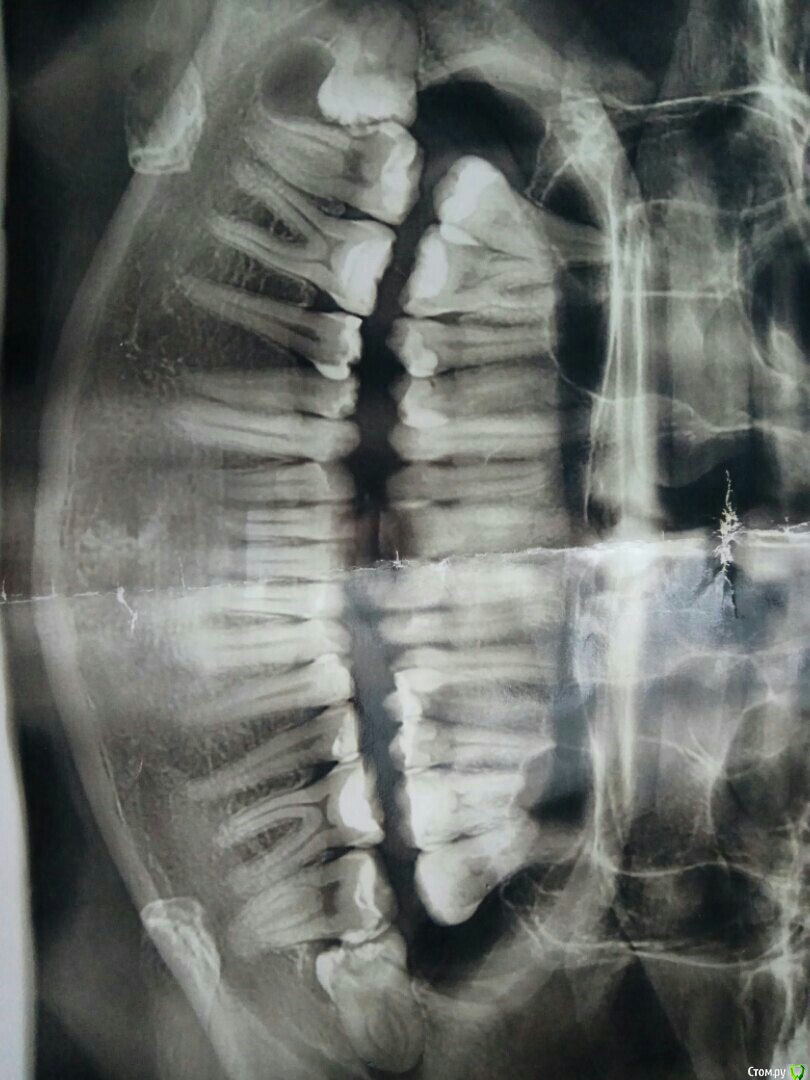

olga85 Опубликовано 28 января, 2018 Поделиться Опубликовано 28 января, 2018 Добрый день ! Очень надеюсь на грамотный ответ доктора ! Большая скученность зубов на ВЧ ортодонт предложила удалить все 8 на НЧ И ВЧ все удалено ! Сейчас неободимо созреть и понять что я делаю все правильно удалить четверки на ВЧ тк мне врач объяснила что если мы не удалим зубы то все сдвинется вперед и я буду как зайчик так ли это на самом деле ? Читала много информации о том что после удаления 4 могут возникнуть головные боли вплоть до панически аттак так ли это на самом деле другие предлагают поставить расширитель .Мне 32 года ! и как лучше удалять до постановки брекетов или поставчт через 2-3 недели удалить ???? Ссылка на комментарий

olga85 Опубликовано 29 января, 2018 Автор Поделиться Опубликовано 29 января, 2018 Действительно ли при удалении возникает головная боль и прочее ? Мне расчеты делали и слепок и ТРГ и панорамный ешение приняла врач однозначно удалять , но я переживаю за последствия может все это слишком раздуто в интернете Дайте ответ професионала по этому поводу ??? Ссылка на комментарий